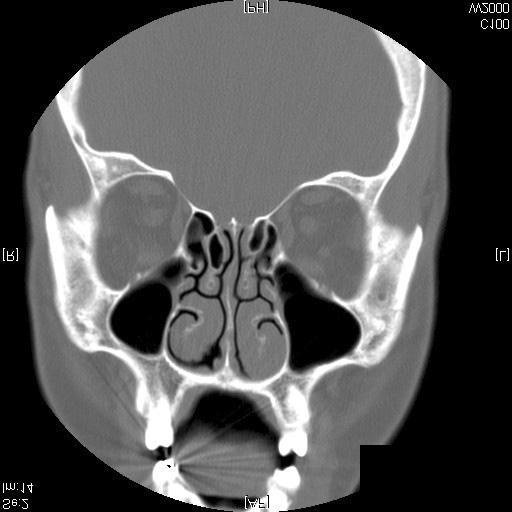

Identify Sphenoid and Maxillary Sinus